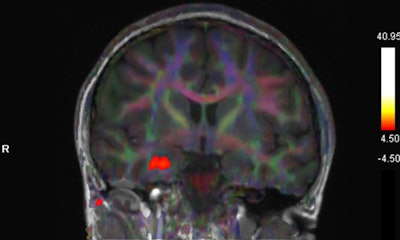

Blood oxygenation level-dependent (BOLD) activation on fMRI studies has been associated with olfactory sensation, a complex activity in the brain that involves the amygdala, the orbitofrontal cortex, and other structures, Gad and Ismail wrote.

"There is accumulating evidence of implication of OFC in patients with COVID-19 with olfactory dysfunction," they noted.

The patient in the case report experienced taste and smell dysfunction for three months and had been referred to a neurology clinic, where she had a normal examination. Clinicians performed a task-based functional MRI study that involved exposure to smells and the generation of BOLD activation maps. Activation was not seen in the orbitofrontal cortex, while there was a strong BOLD signal in the right uncus/piriform cortex, they reported.

"The utility of fMRI in patients with COVID-19 is not well established, and to our knowledge this is the first published report using fMRI in a patient with persistent cacosmia and cacogeusia after COVID-19 infection," they wrote. "Given these findings, we could suggest central olfactory pathway impairment, mainly involving OFC, may be involved in the underlying etiology of persistence of olfactory and gustatory symptoms in patients after COVID-19 infection."